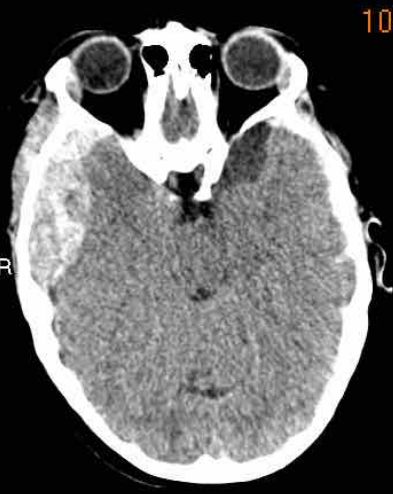

下图一例硬膜下血肿,很难发现(箭头)。

注意,在较高的水平上有双侧硬膜下血肿。

在罕见的情况下,急性硬膜下血肿可能与大脑等密度。

这种情况见于严重贫血、弥散性血管内凝血,或血肿被脑脊液稀释。

当一个慢性硬膜下血肿(>21天)变成低密度,可以和与脑脊液等密度,它可能模拟一个积液。